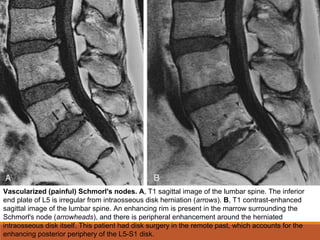

Vascularized (painful) Schmorl's nodes. A, T1 sagittal image of the lumbar spine. The inferior

end plate of L5 is irregular from intraosseous disk herniation (arrows). B, T1 contrast-enhanced

sagittal image of the lumbar spine. An enhancing rim is present in the marrow surrounding the

Schmorl's node (arrowheads), and there is peripheral enhancement around the herniated

intraosseous disk itself. This patient had disk surgery in the remote past, which accounts for the

enhancing posterior periphery of the L5-S1 disk.